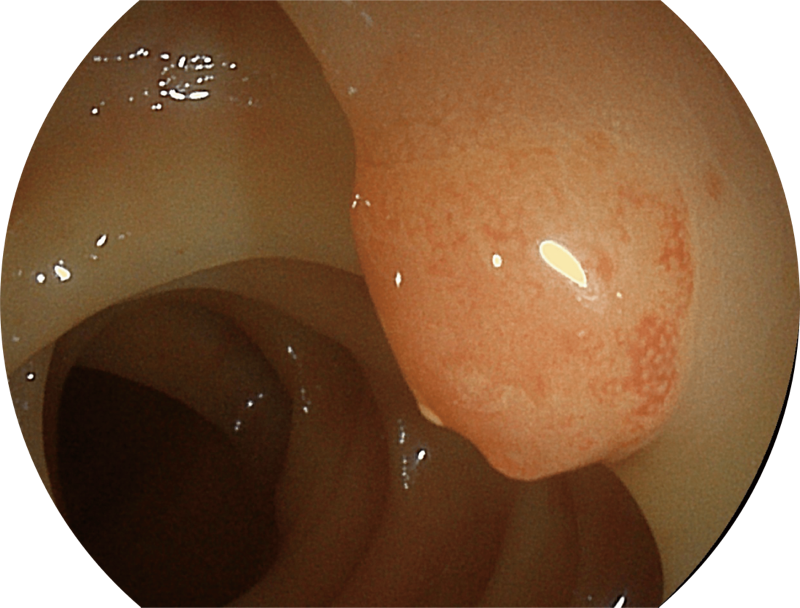

能够凸显黏膜浅层和中层血管轮廓,适用于中、远景观察下的病灶识别和早癌筛查。

(Versatile Intelligent Staining Technology)

能够凸显黏膜浅层血管轮廓和黏膜表面微结构,适用于中、近景观察下的早癌精确诊断。